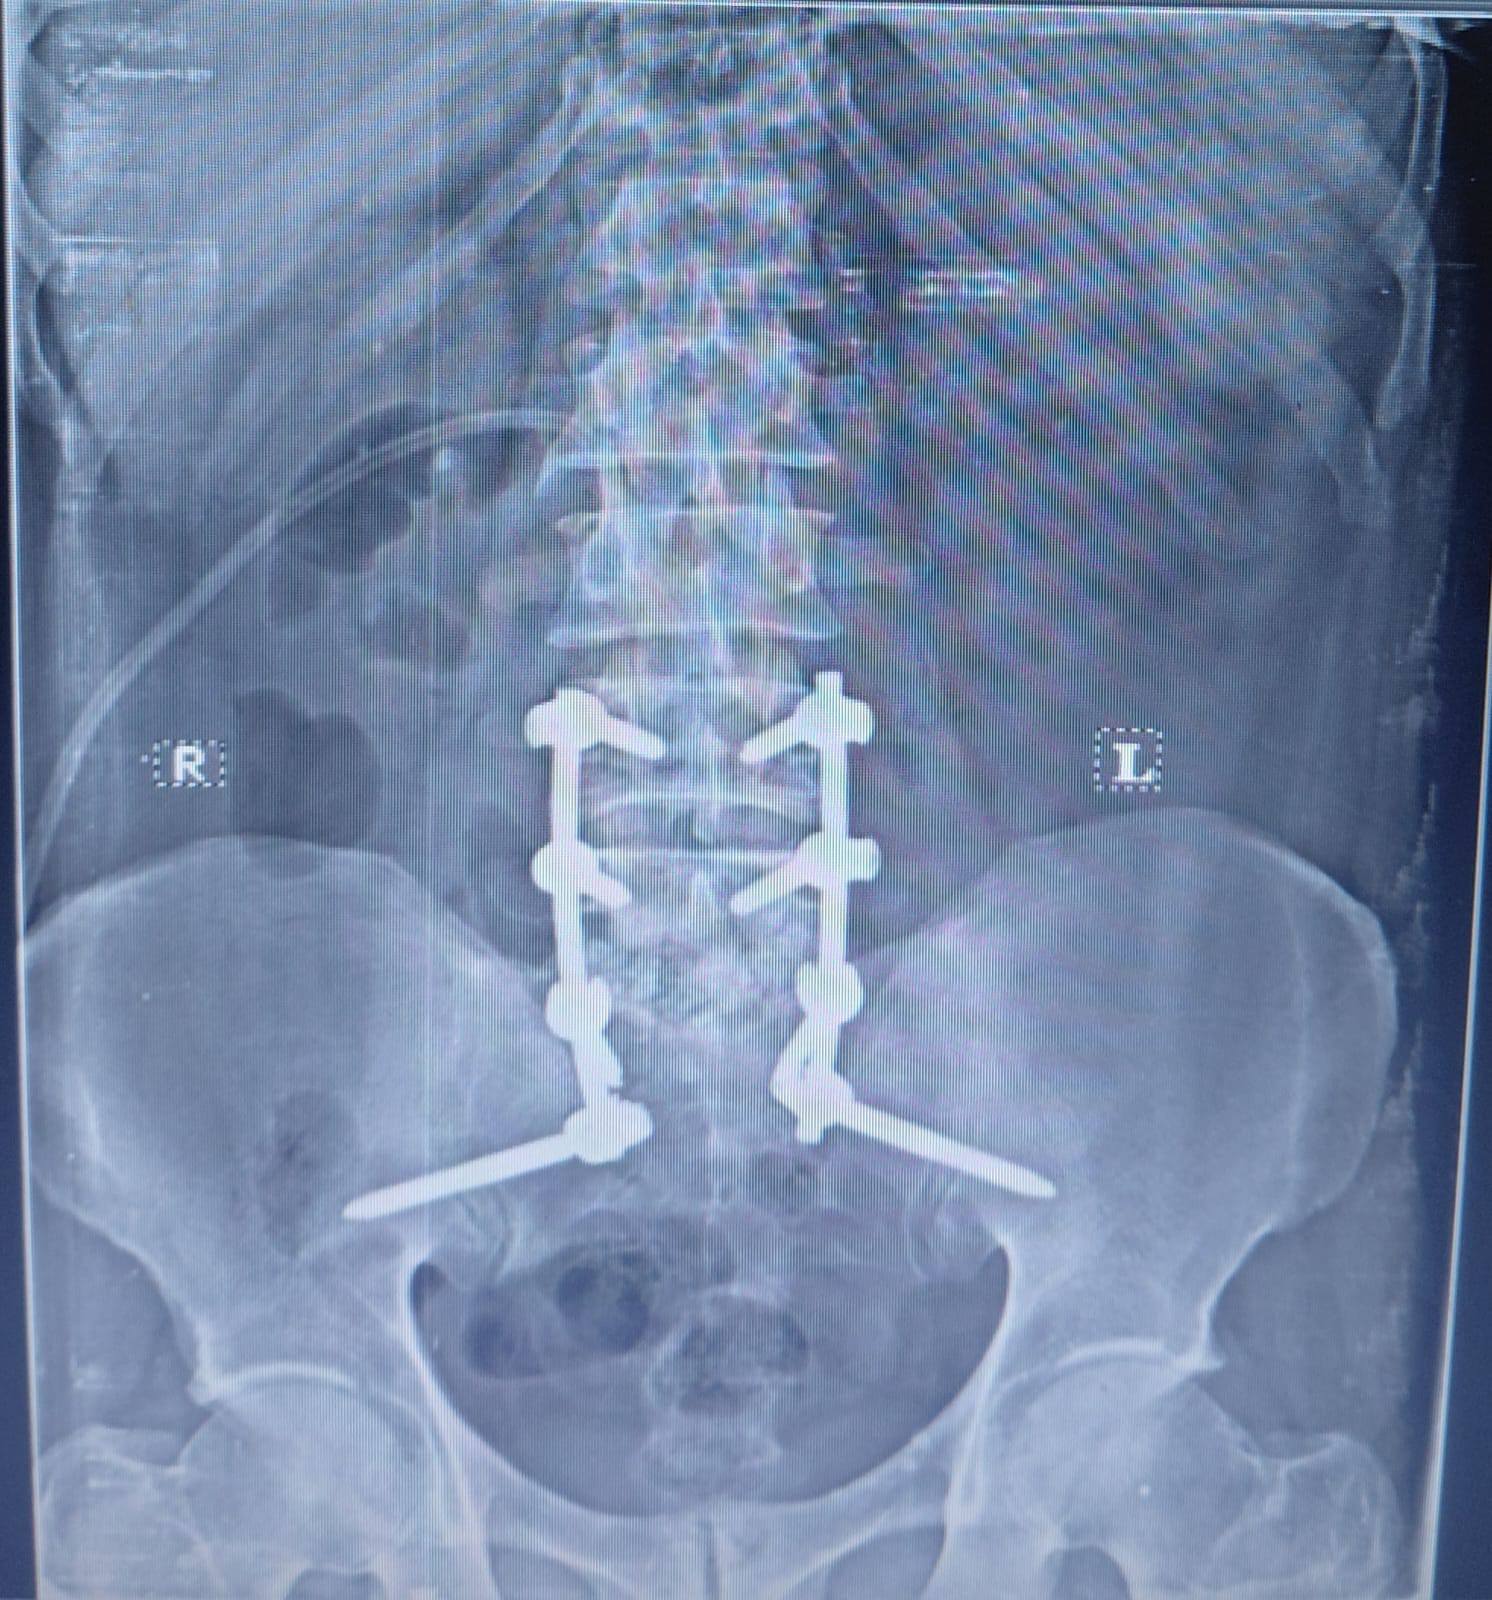

،أ.د/ جمال شمس مدير المستشفى الجامعي الرئيسي،أ.د/ حسام الدين جاد رئيس قسم جراحة العظام نجح فريق قسم جراحة العظام والكسور في إجراء عملية معقدة لالتهاب صديدي بالفقرات مسبب تآكل بالفقرات وضاغط على جذور الاعصاب الطرفية ومسبب ضعف بعضلات الطرفين السفليين مع التأثير على كافة جوانب الحياة للمريض .وقد تمكن الفريق من إزالة الالتهاب والصديد وتثبيت الفقرات وقسم جراحة العظام على أتم استعداد لاستقبال مثل هذه الحالات .